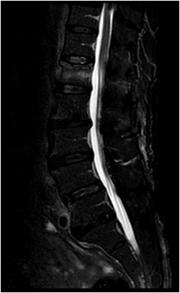

核医学検査は放射線を放出する『放射性同位元素(RI:ラジオアイソトープ)』を用いた検査です。

放射性同位元素に、体内の特定の臓器や病変部に集まる性質をもった物質が混ざった薬を『放射性医薬品』といいます。 放射性医薬品が体内に投与されると、目的とした臓器や病変部に集まっていきます。その様子を専用のカメラで撮影することで、CTやMRIによる形態的な画像情報では得ることのできない、臓器の機能や病態などの情報を得ることができます。